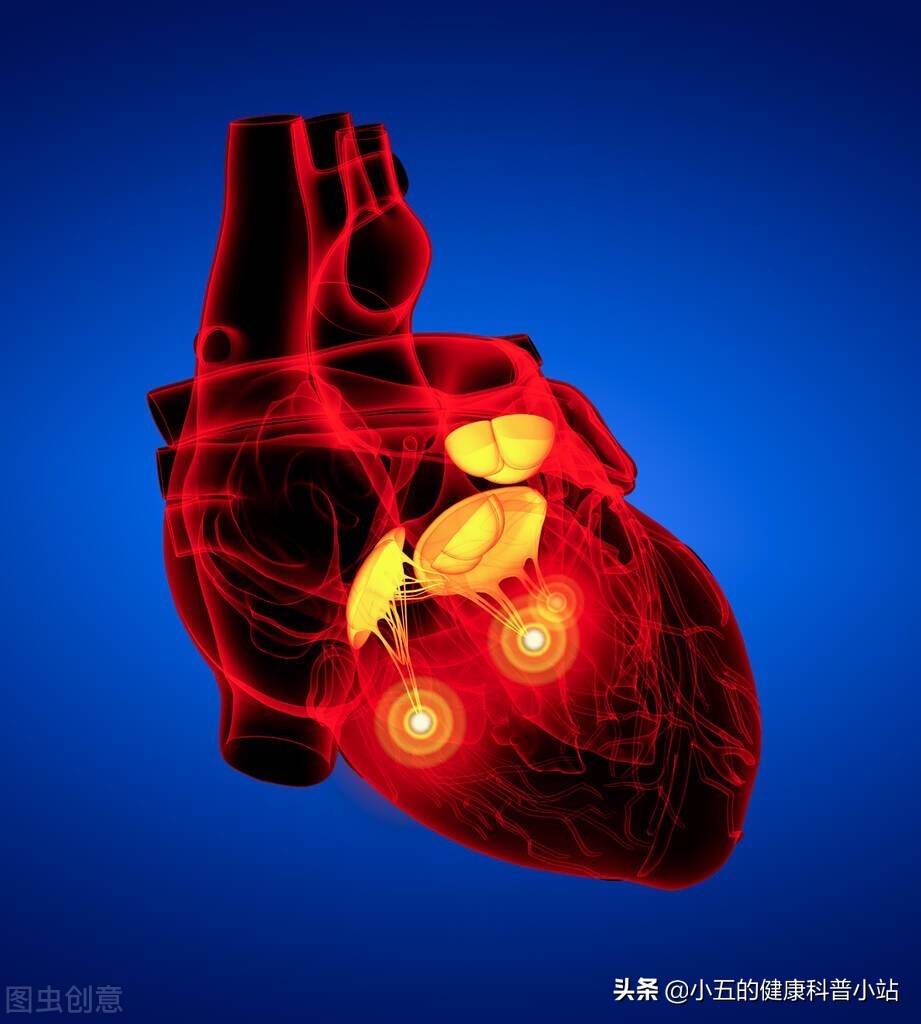

冠状动脉粥样硬化性心脏病,临床也被称为冠心病、缺血性心脏病等,是临床常见的心血管疾病之一,其本质是由于冠状动脉粥样硬化导向血管管腔变窄或者阻塞,从而导致心肌供血、供氧不足而诱发的心脏病。冠状动脉粥样硬化性心脏病好发于中老年人,根据统计我国70岁以上老年人中有60%以上有不同程度冠状动脉粥样硬化,而长期的供血不足会导致心脏损伤,诱发心肌梗死、慢性心衰、心律失常等多种疾病,危险老年人的健康。

临床是针对冠心病的防治是采取抗血小板聚集药联合降脂稳定斑块药作为二线防护,常用的药物包括阿司匹林、氯吡格雷、阿托伐他汀等,这些药物对预防冠心病的加重和发作具有重要意义,但是也有很多人不能耐受药物的副作用,从而求助于中医药,其中心脑宁胶囊就是临床常用于防治冠心病的中成药之一,临床研究表明其可以改善冠状动脉的硬化程度,减轻心肌缺血,从而有效缓解冠心病患者的临床症状,预防疾病加重,同时临床也被用于治疗脑动脉供血不足、脑梗死等多种脑血管疾病,今天就和大家聊一聊这款中成药。

1、冠状动脉粥样硬化性心脏病

临床研究的结果表明心脑宁胶囊可以有效防治冠状动脉粥样硬化性心脏病,改善患者的胸闷、心慌、胸痛等临床症状,同时可以改善患者预后,减少心绞痛的发作次数,临床可与阿司匹林、阿托伐他汀等二线药物联合使用,其被收录于《中成药治疗冠心病临床应用指南(2020年)》等指南中。